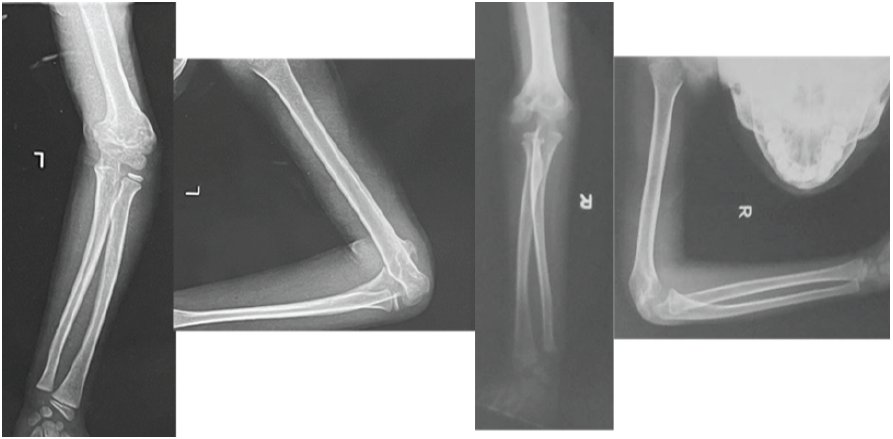

An 8-year-old boy presented with progressive deformity of both elbows (Fig. 1), first noticed after a fall on an outstretched hand 18 months prior (left elbow) and again 12 months prior (right elbow). Both injuries were initially managed traditionally with massage and splints due to a lack of access to orthopedic care during the COVID-19 lockdowns. No radiographs were obtained at that time.

Plain radiographs (Fig. 2) revealed a distal humeral varus deformity with internal rotation on the left and a mild valgus alignment on the right. No evidence of growth plate arrest was observed.

Figure 2: Pre-operative radiographs of both elbows.